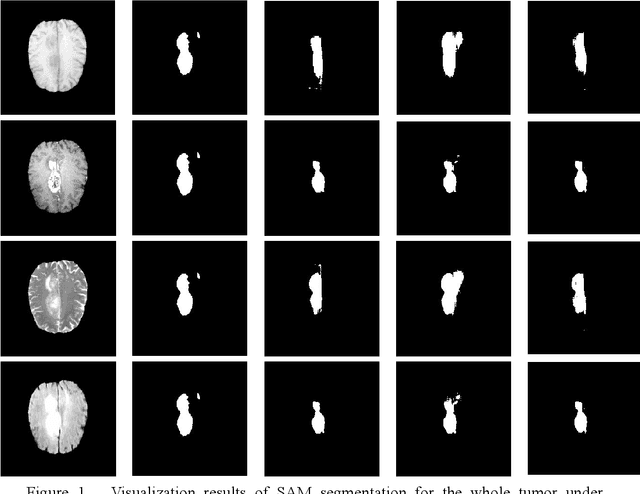

Abstract:Glioma is a prevalent brain tumor that poses a significant health risk to individuals. Accurate segmentation of brain tumor is essential for clinical diagnosis and treatment. The Segment Anything Model(SAM), released by Meta AI, is a fundamental model in image segmentation and has excellent zero-sample generalization capabilities. Thus, it is interesting to apply SAM to the task of brain tumor segmentation. In this study, we evaluated the performance of SAM on brain tumor segmentation and found that without any model fine-tuning, there is still a gap between SAM and the current state-of-the-art(SOTA) model.